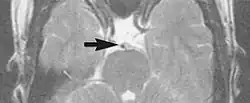

Flow

Flow can manifest as either an altered intravascular signal (flow enhancement or flow-related signal loss), or as flow-related artifacts (ghost images or spatial misregistration). Flow enhancement, also known as inflow effect, is caused by fully magnetised protons entering the imaged slice while the stationary protons have not fully regained their magnetization.[1] The fully magnetized protons yield a high signal in comparison with the rest of the surroundings. High velocity flow causes the protons entering the image to be removed from it by the time the 180-degree pulse is administered. The effect is that these protons do not contribute to the echo and are registered as a signal void or flow-related signal loss (Fig. 2).[1] Spatial misregistration manifests as displacement of an intravascular signal owing to position encoding of a voxel in the phase direction preceding frequency encoding by time TE/2.The intensity of the artifact is dependent on the signal intensity from the vessel, and is less apparent with increased TE.[1]